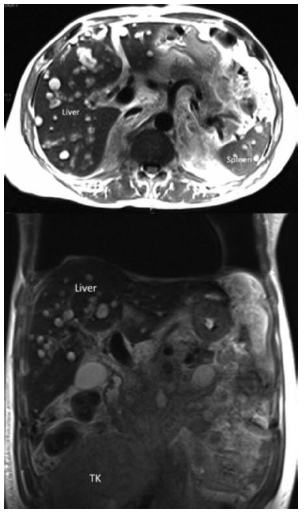

Renal function continued to deteriorate during the following week, requiring initiation of dialysis therapy. Blood and urine and pleural cultures were negative for bacteria, acid-fast bacilli, and fungi. Anti-human herpes virus 8 (HHV-8) antibody was positive, but serologic tests for CMV, BK virus, hepatitis B and C viruses, and human immuno-deficiency virus were negative. A noncontrast magnetic resonance image (MRI) of the abdomen showed a “bulky” transplanted kidney and multiple well-defined lesions of variable sizes in the liver and spleen (Figure 1).

Mycophenolate and tacrolimus were withdrawn. Prednisolone was continued, and sirolimus was added to prevent acute graft rejection. During the next 2 months, his general condition improved and he gained 4 kg of weight. Follow-up ultrasonography 3 months later showed complete resolution of hepatic lesions. Subsequent ultrasonography and MRI studies over the next 6 months confirmed complete resolution of Kaposi sarcoma lesions in the liver and spleen and progressive decreases in size and volume of kidney allograft (Figure 4). Despite radiologic regression of Kaposi sarcoma, renal transplant function did not recover. Repeat renal biopsy was not performed. Immunosuppression was gradually tapered off, and no signs of graft intolerance syndrome were seen. Sixteen months after the diagnosis of Kaposi sarcoma, the patient is in complete remission, although he is dependent on dialysis.

Figure 1. Abdominal Magnetic Resonance Image Showing Multiple Kaposi Sarcoma Lesions in Liver and Spleen and “Bulky” Transplanted Kidney (TK)

Figure 4. Follow-Up Abdominal Magnetic Resonance Image Showing Complete Resolution of Kaposi Sarcoma Lesions in Liver and Spleen and Decrease in Size of Transplanted Kidney (TK)